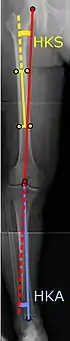

To indicate knee replacement in case of osteoarthritis, its radiographic classification and severity of symptoms both should be substantial. Such radiography should consist of weightbearing X-rays of both knees: AP, lateral, and 30 degrees of flexion. AP and lateral views may not show joint space narrowing, but the 30-degree flexion view is most sensitive for narrowing. Full-length projections also are used in order to adjust the prosthesis to provide a neutral angle for the distal lower extremity. Two angles used for this purpose are:

- Hip-knee-shaft angle (HKS),[10] an angle formed between a line through the longitudinal axis of the femoral shaft and its mechanical axis, which is a line from the center of the femoral head to the intercondylar notch of the distal femur.[12]

- Hip-knee-ankle angle (HKA),[11] which is an angle between the femoral mechanical axis and the center of the ankle joint.[12] It is normally between 1.0° and 1.5° of varus in adults.[13]